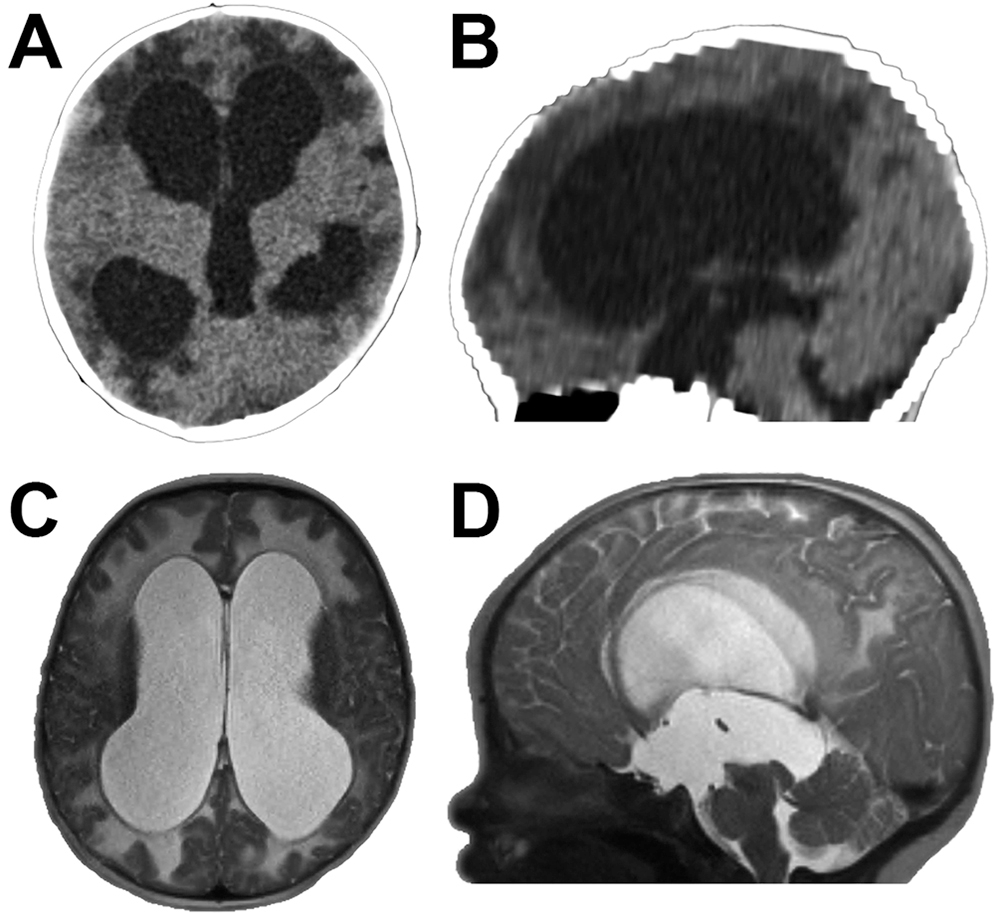

頭部CT顯示腦室擴(kuò)大,符合阻塞性腦積水(圖1 a和B)。高分辨率結(jié)構(gòu)磁共振成像發(fā)現(xiàn)沒有腫瘤的跡象或其他軟組織腫塊(圖1c和D)。腦導(dǎo)水管似乎錐度的喙的程度與正常四腦室(圖1 D)。根據(jù)患者的臨床表現(xiàn)和影像學(xué)表現(xiàn),我們?cè)\斷為導(dǎo)水管狹窄。

圖1:表現(xiàn)為明顯的導(dǎo)水管狹窄。A和B:CT軸位(A)和矢狀位(B),患者2個(gè)月時(shí)一次就診,顯示三腦室擴(kuò)大。C和D:初診時(shí)獲得軸向(C)和矢狀(D)t2加權(quán)MR圖像,顯示三腦室擴(kuò)大,四腦室大小正常,嘴側(cè)腦導(dǎo)水管變細(xì),與導(dǎo)水管狹窄一致。